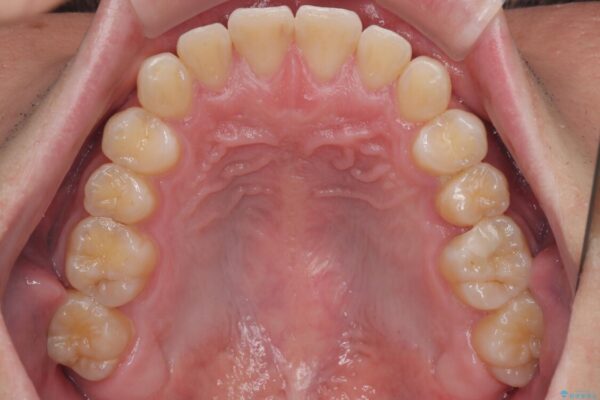

・上顎左右の第二大臼歯が頬側へ転移し、シザーズバイト(scissors bite)の状態

・上顎左側第二小臼歯が90度捻転しており、噛み合わせに影響

治療前

• 前歯のガタガタ・奥歯のかみ合わせ(シザーズバイト)を改善|1年半で完了したメタルブラケット矯正 治療前画像